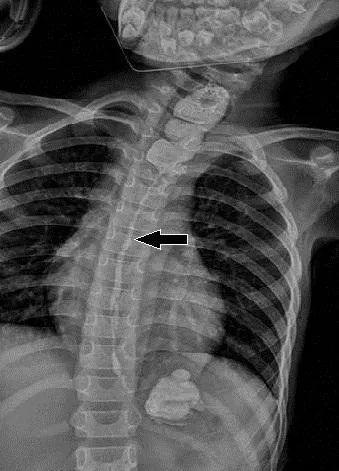

文章插图

术后造影食管恢复正常 通讯员供图

经过科室联合多学科团队的讨论 , 最终决定采取经颈腹联合切口胃代食道术 , 即裁剪下小丽的一部分胃 , 去替代她已经萎缩的食管 。 手术难度非常大 , 国内外仅有少量案例报道 。 经过7个小时的奋战 , 手术终于顺利地结束了 , 在经过后期的护理后 , 小丽慢慢恢复正常饮食了 , 目前已顺利出院 。